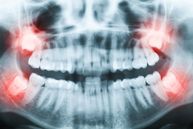

Weisheitszahn-Beschwerden

Weisheitszähne können zu sehr unterschiedlichen Beschwerden führen. Die eigentliche Ursache ist begründet in einem Missverhältnis zwischen der Kiefergröße und der Anzahl der Zähne. Durch den entstehenden Platzmangel können sich die Weisheitszähne nicht mehr in den normalen Zahnbogen einordnen, brechen an der falschen Stelle durch oder verschieben die vorhandenen Zähne.

Folgende Beschwerden können auftreten:

• Ein bis zum Schmerz gehendes, unbestimmtes Druckgefühl bei noch verlagerten oder schon durchgebrochenen Weisheitszähnen.

• Durch die relativ zu kleinen Kiefer kommt es bei dem fortschreitenden Wurzelwachstum der sich entwickelnden Weisheitszähne häufig zu einem Engstand, so dass sich ursprünglich korrekt stehende Zähne übereinanderschieben.

• Wenn die Weisheitszähne durchbrechen, bilden sich häufig Zahnfleischtaschen aus, die sich mangels Pflegemöglichkeit entzünden. Mundgeruch, Entzündungen und sogar Abszesse sind hier häufige Begleiterscheinungen.

• Durch die fehlende Pflegemöglichkeit im hinteren Zahnbereich kommt es zu Belagbildung, Entkalkung und letztendlich Karies.

Bei nur zum Teil verlagerten Weisheitszähnen wird auch die Pflege der hinteren normalen Zähne zum Problem, so dass die letzten Zähne - wenn man zu lange mit der Weisheitszahnentfernung wartet - von der Rückseite her und recht weit unten kariös werden. Diese Befunde werden häufig zu spät erkannt, da die Karies bei der Untersuchung nicht offensichtlich ist und nur auf dem Röntgenbild zu sehen ist. Wenn dann Schmerzen an diesen Zähnen auftreten, ist häufig eine Rettung nicht mehr möglich, so dass der Weisheitszahn und der letzte Zahn gleichzeitig entfernt werden müssen.